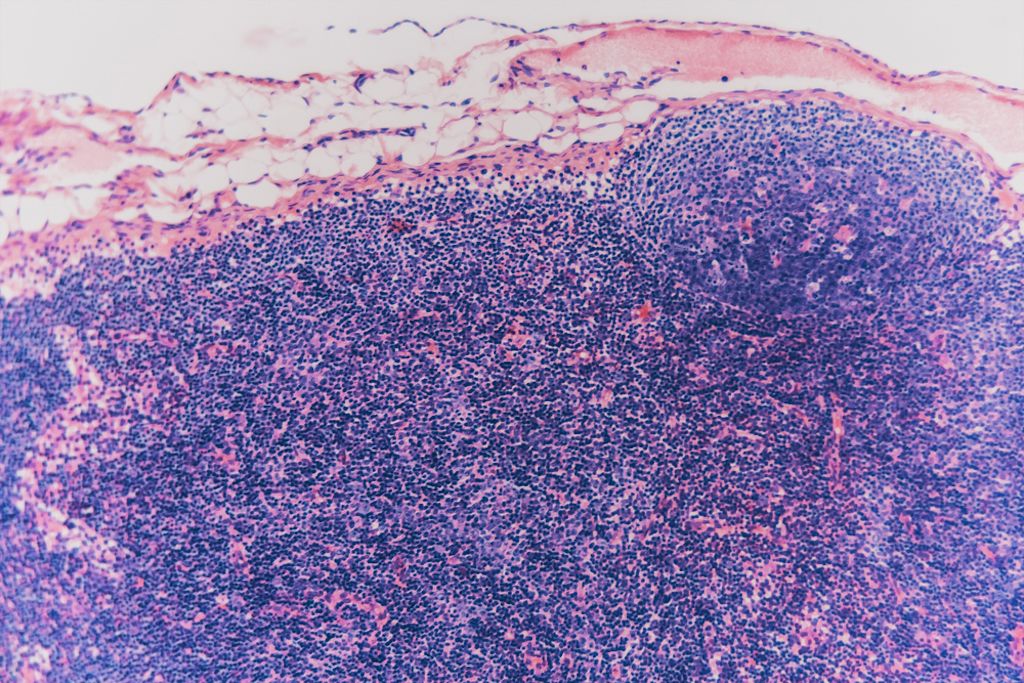

Wann ist eine Lymphknoten-Biopsie notwendig?

Eine Lymphknoten-Biopsie beim Hund wird notwendig, wenn ein Lymphknoten ungewöhnlich geschwollen oder vergrößert ist und die genaue Ursache der Veränderung unklar bleibt. Diese Schwellungen können durch verschiedene Gesundheitsprobleme hervorgerufen werden, wie Infektionen, Entzündungen oder Krebs (z. B. Lymphome). Eine Biopsie hilft dabei, die Ursache zu bestimmen und die geeignete Behandlung festzulegen.

Die Biopsie wird üblicherweise durch eine Feinnadelaspiration oder eine Stanzbiopsie durchgeführt, wobei eine Probe des Lymphknotengewebes entnommen und im Labor untersucht wird, um festzustellen, ob Entzündungen, Infektionen oder Krebs vorliegen.